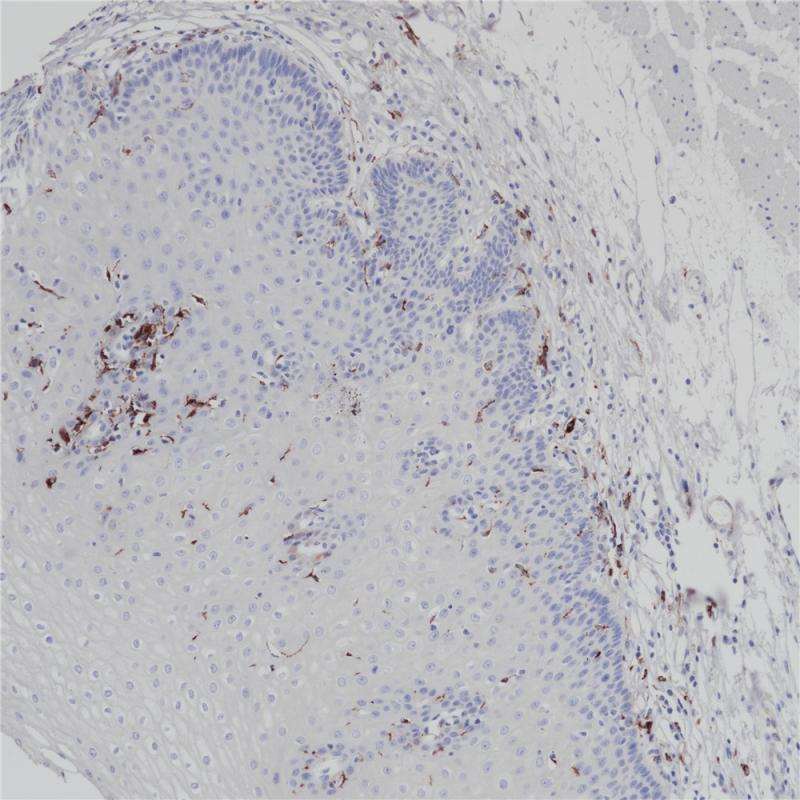

MHC II(DRα chain) 重组兔单克隆抗体

主要组织相容性复合体 II 类(MHC II 类)分子是在巨噬细胞、树突细胞和 B 细胞等抗原呈递细胞表面表达的异二聚体的跨膜糖蛋白。在人体中,MHC II 类蛋白复合体被人白细胞抗原基因复合体 (HLA) 编码。MHC II可在 B 淋巴细胞、活化的 T 淋巴细胞、活化的自然杀伤 (NK) 细胞等表达。

阳性对照

食管